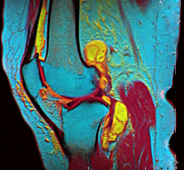

In addition, variants of false color such as pseudocolor (see discussion), density slicing (see discussion), and choropleths (see discussion) are used for information visualization of either data gathered by a single grayscale channel or data not depicting parts of the electromagnetic spectrum (e.g. elevation in relief maps or tissue types in magnetic resonance imaging).

A pseudocolor image (sometimes styled pseudo-color or pseudo color) is derived from a grayscale image by mapping each intensity value to a color according to a table or function.[7] Pseudo color is typically used when a single channel of data is available (e.g. temperature, elevation, soil composition, tissue type, and so on), in contrast to false color which is commonly used to display three channels of data.[4]

Depending on the table or function used and the choice of data sources, pseudocoloring may increase the information contents of the original image, for example adding geographic information, combining information obtained from infrared or ultra-violet light, or other sources like MRI scans.[8]